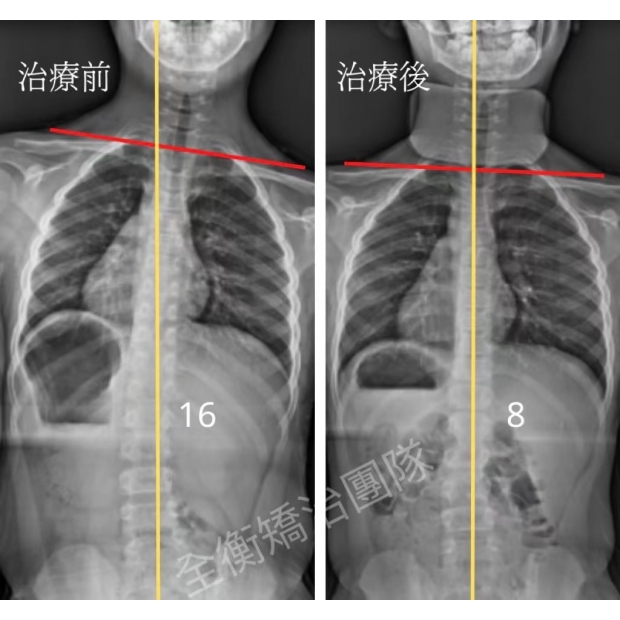

16歲女生,青春期末期才發現側彎,還有機會嗎?16歲女生,青春期末期才發現側彎,還有機會嗎?

16歲妹妹,高一健檢才發現脊椎側彎

經過一年的復健和追蹤

側彎角度由29度進步至15度,減少50%!

旋轉也從12度減少到6度 -